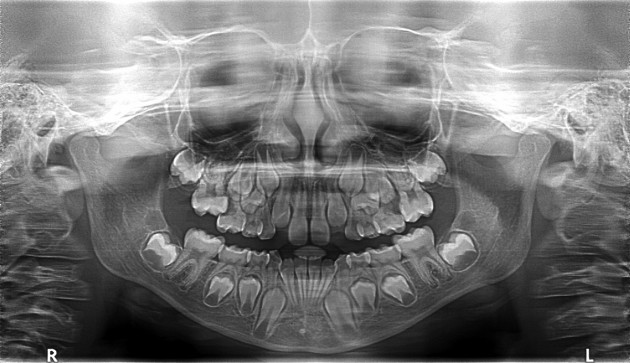

Im Laufe unseres Lebens bekommen wir zwei Sätze von natürlichen Zähnen - für die Dritten müssen wir dann selbst sorgen. Die sog. Milchzähne erscheinen im Alter von sechs Monaten, und werden von den bleibenden Zähnen etwa ab dem sechsten Lebensjahr abgewechselt. Bestimmt hat sich schon jeder einmal gefragt, warum Milchzähne Milchzähne heißen - Hippokrates war sich sicher, dass diese während der Stillzeit aus der Milch geformt werden. Das bleibende Gebiss besteht üblicherweise aus zweimal 16 Zähnen, und bis sie alle durchgebrochen sind, ist man erwachsen. Als letzte erscheinen dann die Weisheitszähne. Die Bezeichnung entstand, weil man in früheren Zeiten, als die Lebenserwartung erheblich niedriger war, im Alter von 20 Jahren schon über genügend Lebenserfahrung verfügte. Bei den meisten Menschen brechen diese hintersten Mahlzähne bis zum 25. Lebensjahr durch. Im Laufe der Entwicklungsgeschichte hat sich aber unser Kiefer verkleinert, sodass die Weisheitszähne kaum noch Platz haben, und nur zum Teil oder gar nicht durchbrechen können. Weisheitszähne sind somit ein Stück Evolutionsgeschichte.

| Zahnwechsel: Milchzähne werden durch bleibende Zähne herausgestoßen |